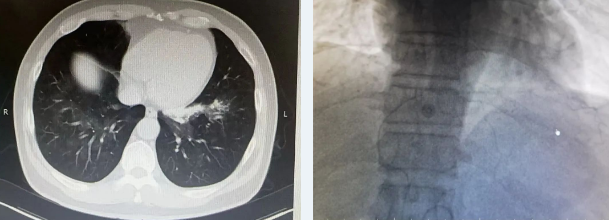

时间就是生命!呼吸与危重症医学科张喜霞医生接诊了该患者,经检查问诊后,考虑患者出血原因不明,且仍存在较大风险,随时可能危及生命,张大夫紧急邀请了普外科会诊,普外科何永健主任医师根据其病史及相关检查结果考虑左肺病变处出血与右膈动脉相关,决定为行支气管动脉造影加栓塞术,并迅速送入导管室做进一步的检查救治。

抢救过程中,医护人员争分夺秒,与死神赛跑。在导管室的检查救治过程中,患者又突发大咯血,呼吸困难,大量鲜血经口鼻涌出,现场紧急给予积极吸引器及清洗口鼻,患者意识丧失、口唇及皮肤发绀,血氧饱和度降至30-40%、心率降至40次/分,紧急请麻醉科气管插管、留置导尿,插管成功后继续给予栓塞病变血管手术,并在支气管镜检查辅助下,清楚看到并及时吸出支气管内大咯血血块,患者血氧饱和度恢复至96-98%,患者生命体征恢复,转入ICU继续治疗。

北京燕化医院副院长、呼吸与危重症医学科主任、主任医师李小明为患者行气管镜下气道持续冲洗,吸出大量鲜血,清理气道内淤血,镜下发现左肺出血,及时给予止血药物局部止血治疗。为避免患者再次出血出现窒息,向家属说明情况并征得家属同意后,麻醉科医师给予行右肺单侧通气。